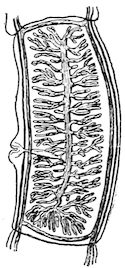

Fig. 1.—Rachitis in a young goat.

Rachitis is a disease of youth, and is common both to the human species and to all domestic animals. It is characterised by irregularities in development and by imperfect consolidation of the bones. The boundary between rachitis and osseous cachexia is difficult to define and in fact at the present moment the two diseases can scarcely be defined with exactitude. Rachitis again is often complicated with softening of the bones, disease of the limbs, arrested development, etc., but it must not be forgotten that although the irregularities in ossification and development of the skeleton are the symptoms most striking to the eye, they do not stand alone, and that from the point of view of development all the tissues, including the muscles, are more or less affected and that most of the physiological functions such as digestion and the secretion of urine are deranged.

Symptoms. The onset is absolutely insidious and the diagnosis of rachitis is never made until nutrition has long been abnormal.

This disturbance of nutrition is revealed by irregularity and abnormality in appetite, by difficulty in rising and moving about, and by the animals lying down for long periods. The subjects are feeble, sluggish and badly developed.

Next supervenes the second phase characterised by deformity of bones. This is of two kinds—deformity in the neighbourhood of joints (deformity or enlargement of the epiphyses) and deformity of the diaphyses. The former results from irregularity in ossification of the articular cartilages. The latter is followed by loss of rigidity in the bones of the limbs which, under the influence of the body weight and of muscular contraction, bend in different directions.

The bones appear of increased thickness principally towards the 6articulations. The latter are deformed, and on palpation are found to be surrounded by uneven and irregular growths.

The front limbs are distorted. In young pigs, lambs, and less frequently in foals, calves and dogs, the jaws become deformed, and mastication is rendered difficult.

The vertebral column may also be affected, and lordosis (bending downwards of the back) or skoliosis (lateral bending of the back) is somewhat frequent.

Cyphosis, or upward bending of the back, seldom occurs, and when seen, sometimes results from disease other than rachitis.

General development is always interfered with and the young creatures are generally dwarfed.

The digestive apparatus is disordered, the appetite is irregular and sometimes depraved, while indigestion, gastritis, and enteritis are not exceptional. Physiological and pathological research has shown that the quantity of phosphoric acid eliminated in twenty-four hours in a rachitic child is double the quantity passed by a healthy infant. The amount of urea in the urine (which is a criterion of nutrition, and usually varies in proportion to the amount of food ingested) is, on the contrary, diminished even when highly nitrogenous food is given, thus suggesting diminution in nutrition.

Lesions. The lesions are represented by abnormal and irregular thickening around the interarticular cartilages. The cartilage is thickened, compressible, very spongy and without regular ossification. Diffused periostitis exists principally towards the extremities of the bone. Beneath the periosteum the surface of the bone appears rough and softened. On section the medullary canals are seen to be enlarged and filled with marrow of a gelatinous character. The Haversian canals are dilated, and the entire tissue appears very vascular. Chemical analysis proves that the mineral constituents of the bone, particularly the phosphates, have diminished by one-half; the organic constituents on the other hand are increased in a similar ratio, but the ossein is abnormal. Ossification has, in a word, been incomplete.

7Diagnosis. Diagnosis presents no difficulty except in the early stages before deformity has occurred.

Rachitis can scarcely be mistaken for any other condition except perhaps infectious rheumatism, but the rapid course of the disease in the latter case, the persistence of fever and the swelling of the joint cavities sufficiently differentiate the conditions provided care is exercised.

Prognosis. From an economic point of view the prognosis is very grave for if the lesions are extensive there is nothing to be gained by keeping the animal.

Treatment. Treatment differs very little, whether the animals are still being suckled or have been weaned. In the former case it is necessary to improve the quality and chemical constitution of the mother’s milk by giving food, richer both in mineral salts and in nitrogenous material.

Cooked grains, milk, and forage of good quality should be given freely. When the mothers are exhausted and anæmic it is better to feed the little animals artificially or to change them to a foster-mother. Those already weaned should be given good rich milk, eggs, boiled gruel, and drugs, such as the phospho-chlorate of lime, 1 to 1½ drachms per day (for a calf); lacto-phosphate of lime, 1 to 1½ drachms; bi-phosphate of lime, 1 drachm, or simply ordinary phosphate of lime. Oil containing 1 per cent. of dissolved phosphorus may be given in doses of 1 to 2½ drachms, according to the size of the calves, but its use calls for much care, and it should only be given for alternate periods of a fortnight. The glycerophosphates are not very active. Beef meal in doses of 6 drachms to 1½ ounces and chloride of ammonium in doses of 30 to 60 grains have also been used advantageously. The above drugs, but particularly the bi-phosphate of lime and chloride of ammonium, stimulate nutrition and diminish the quantity of phosphoric acid eliminated.